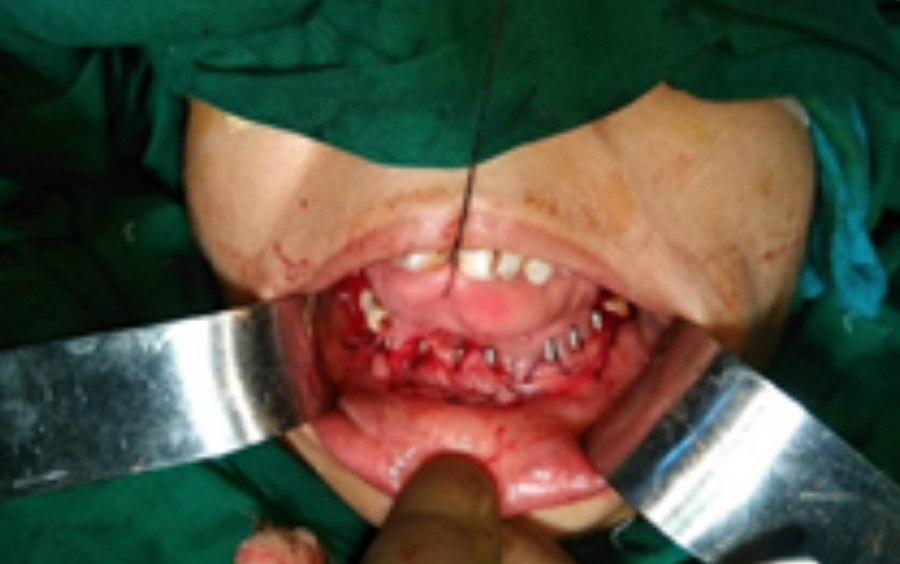

After testing and resulting pathology reports the diagnosis was concluded as a Ameloblastoma of mandibular anterior region

Dr. Abdul Hameed, a well-known at Tanjawar Hospital, Mumbai studied the patient’s CT scan images. After doing so he concluded the need for patient specific Mandibular implant.

Implant was manufactured under ISO 13485 guidelines & tested to give an accurate fit & utmost safety. Implant was made as per anatomical requirement, contour, and bone thickness which are patient specific. This implant also boasts of faster recovery, less invasiveness and lower risk. As the implant is accurately placed, it is aesthetically perfect, which boosts mental and physical state of the recipient allowing her to return to her normal routine life within a very less time.